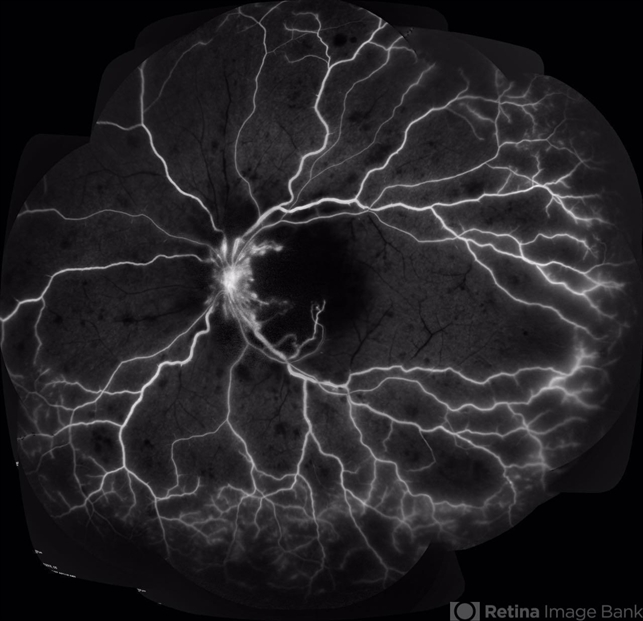

- vasculitis, systemic lupus erythematosus (SLE) vasculitis

- 28-year-old white man was referred to the rheumatology clinic with gradually and rapid deterioration of the vision (both eyes). In this picture, we can observe vasculitis (leakage from vessels) and diffuse ischemia in the left eye.